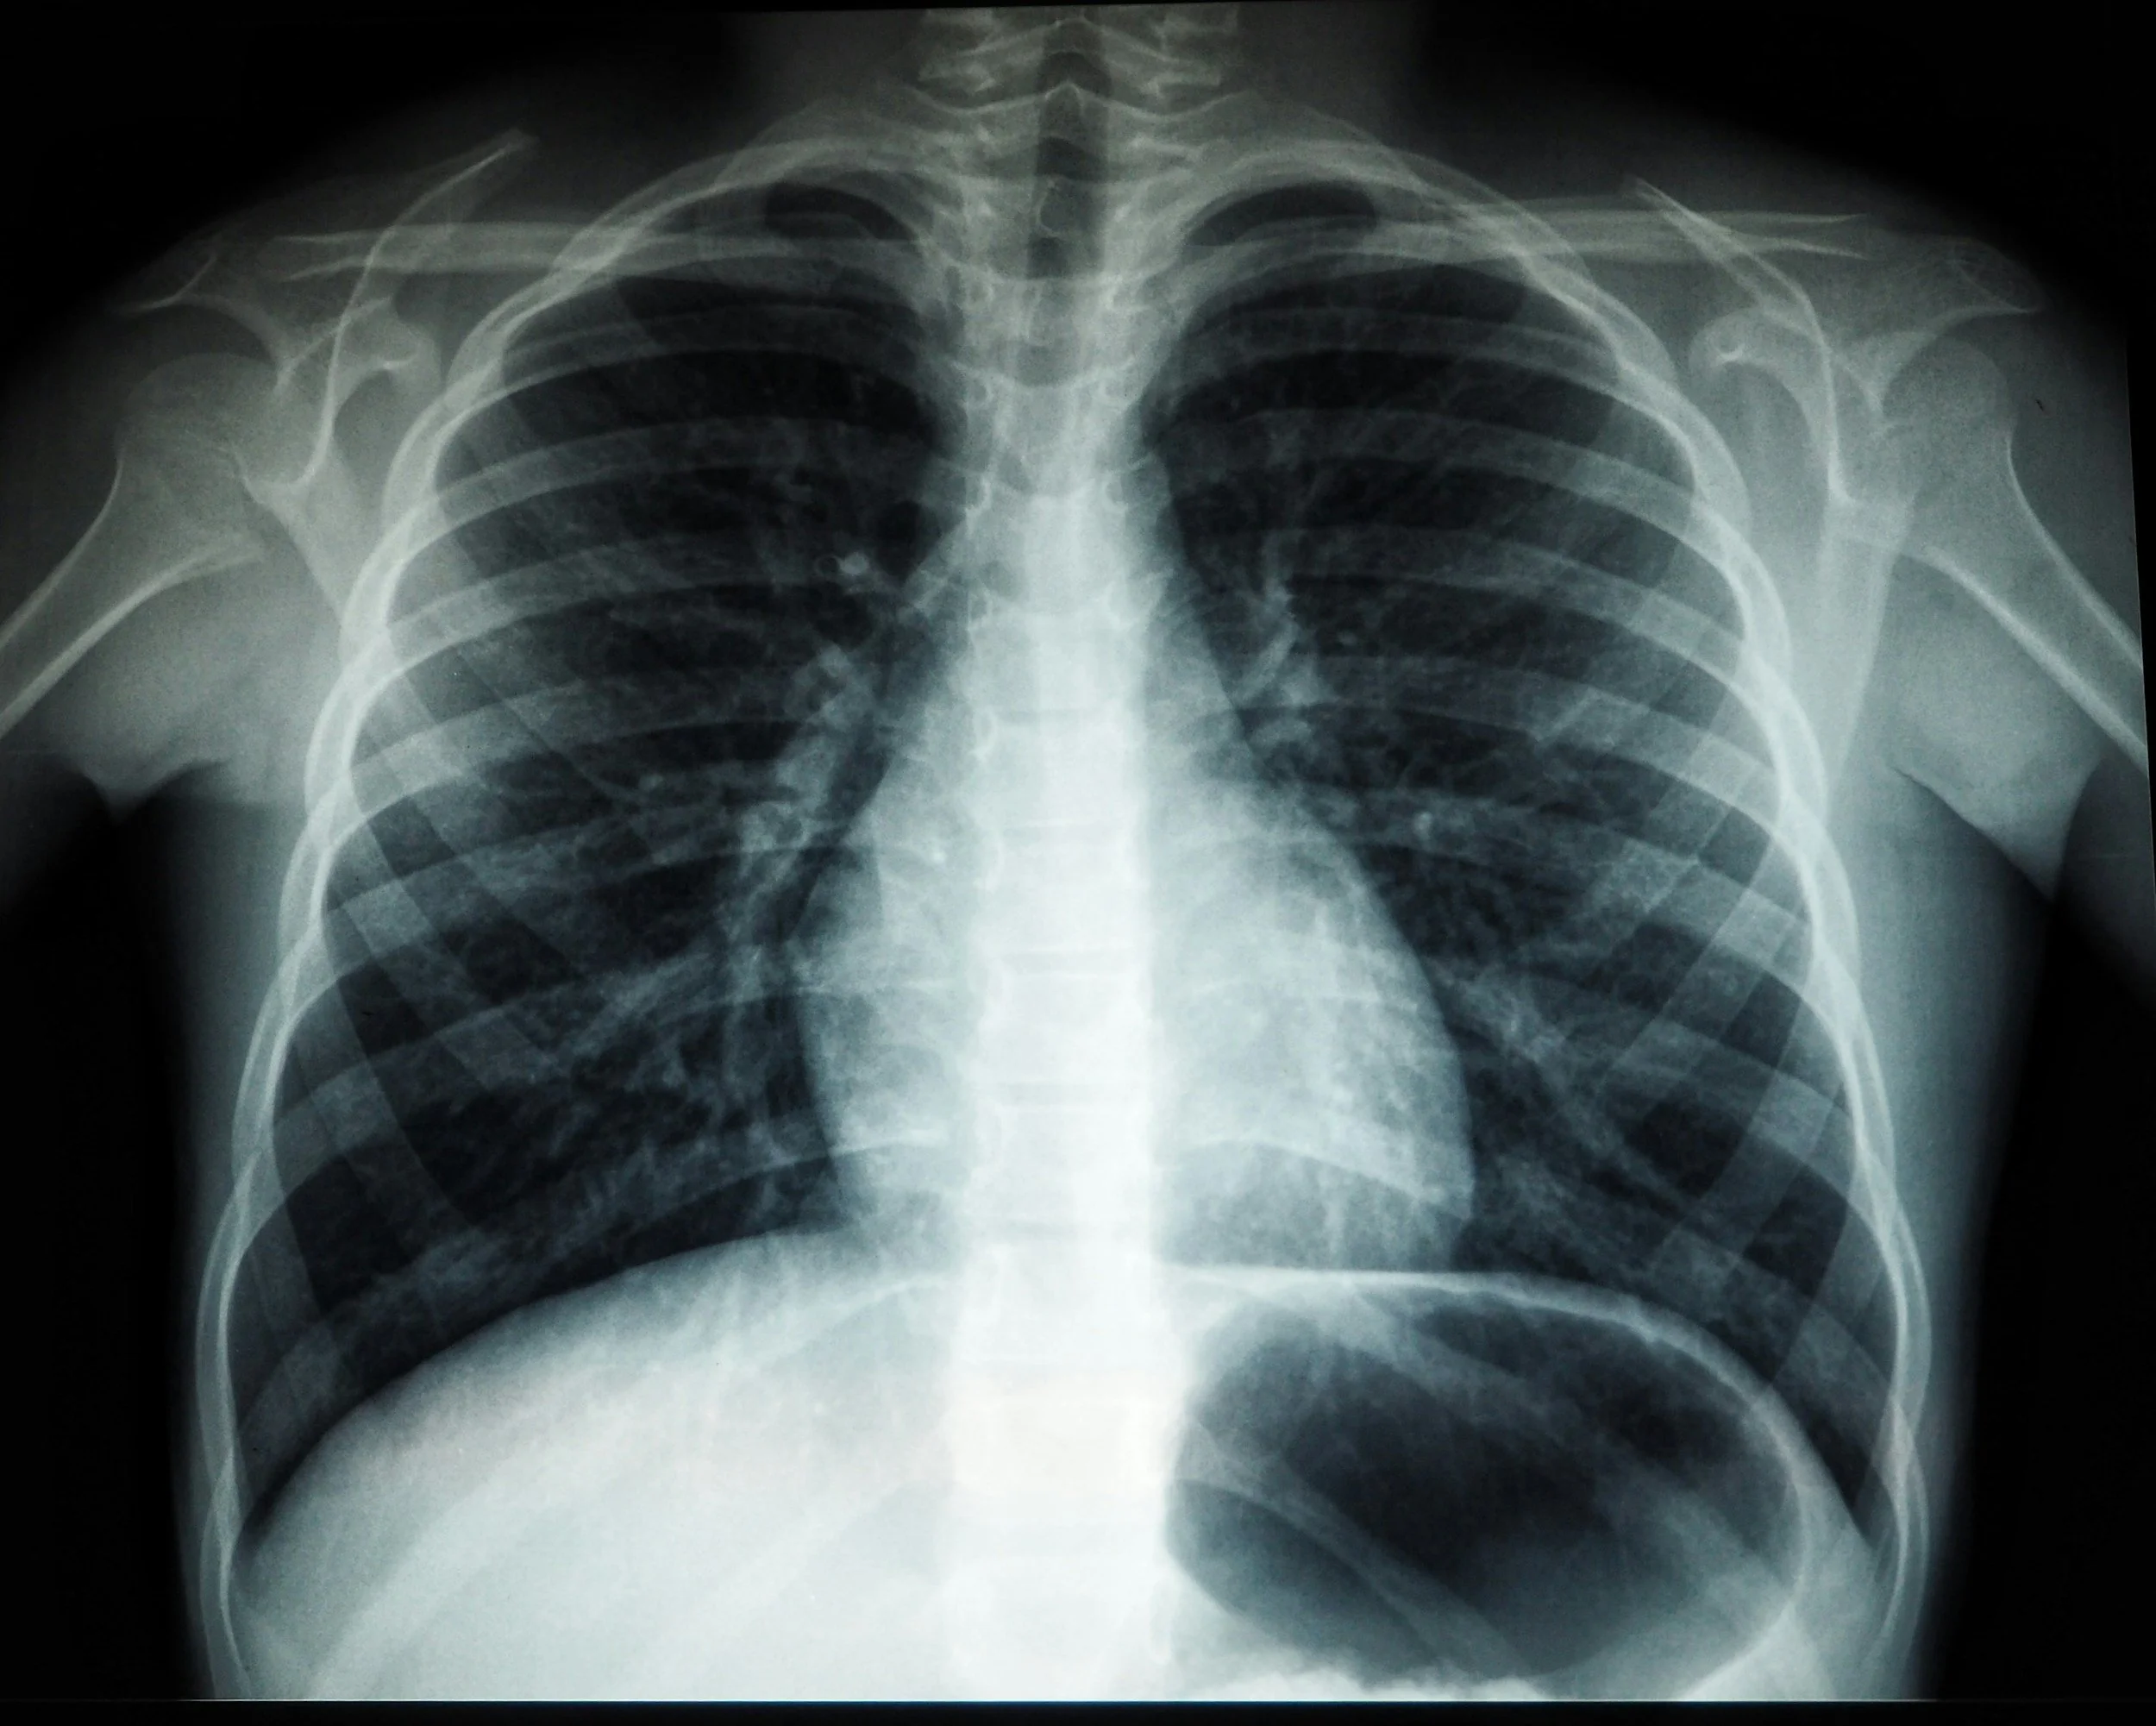

Lung cancer is the leading cause of cancer death around the world and low-dose chest computed tomography (LDCT) is recommended to screen people between 50 and 80 years old who have a significant history of smoking or currently smoke.

Lung cancer screening with LDCT has been shown to reduce deaths from lung cancer by up to 24 percent, but as rates of lung cancer climb among nonsmokers, new strategies are needed to screen and accurately predict lung cancer risk across a wider population.

Sybil is a deep learning model that accurately predicts a patient’s risk of lung cancer up to six years in advance from analyzing a low-dose CT scan, ensuring that lung cancer is detected in its earliest stages. Sybil's accuracy has been validated across multiple retrospective datasets and real-world cohorts through 2025 and early 2026, demonstrating its ability to predict lung cancer risk with high precision.

Sybil research paper: “Sybil: A Validated Deep Learning Model to Predict Future Lung Cancer Risk From a Single Low-Dose Chest Computed Tomography”